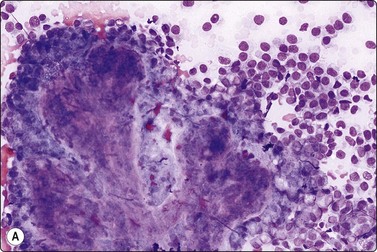

Fig. 7.8 Lactating breast

Dispersed acinar cells with abundant pale and fragile cytoplasm, rounded nuclei and prominent central nucleoli; background of lipid secretions (A, MGG, HP; B, H & E, HP oil); (C) Corresponding tissue section (H&E, IP).

Criteria for diagnosis

Cellular smears,

Poorly cohesive, mainly dispersed epithelial cells of acinar type,

Cells have abundant fragile cytoplasm with secretory vacuoles and frayed borders,

Rounded vesicular nuclei and central nucleoli,

Dirty background due to lipid secretion and stripped nuclei with prominent nucleoli,

Single bipolar nuclei difficult to find.

FNB is very useful in reducing surgical intervention to a minimum during pregnancy and lactation. The pattern seen in FNB smears of ‘lumps’ in a pregnant or lactating breast can be problematic to inexperienced eyes and cause concern for malignancy.93,94 Smears are usually cellular. The cells are enlarged and arranged in loose groups or singly. The cells have an abundant fragile cytoplasm, vacuolated and finely granular. Nuclei are round, central, larger than the usual ductular cells, and have distinct small nucleoli (Fig. 7.8B). Some epithelial nuclei are stripped of cytoplasm. Single naked bipolar/oval nuclei are difficult to find. The background of abundant milky secretion with numerous lipid droplets seen as vacuoles is characteristic of actively secreting breast tissue and is the main clue to the diagnosis (Fig. 7.8A).